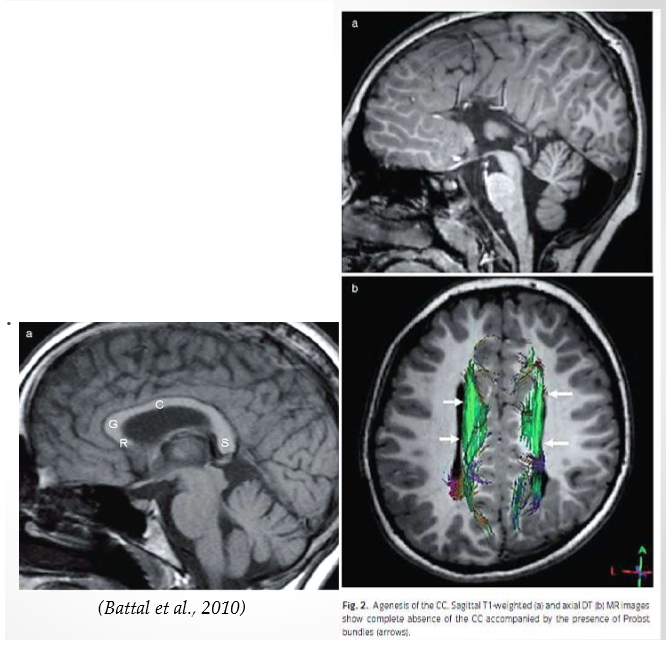

Agenesis of the Corpus Callosum

Lack or partial lack of the CC. Fibers migrate ipsilaterally & course along the lateral

ventricles forming Probst bundles. Not connected. Can function without the corpus callosum. Few observable symptoms.

Agenesis of the CC (AgCC)

1:4000 live births. Few observable symptoms…is there compensation by other connections (i.e., the anterior commissure)? Actually perform better than adults on the split-brain test. Developmentally not the same, however have average IQ scores. These symptoms occur in various combinations and severity. Spectrum of how effected you are and of symptoms. Sounds similar to Autism.